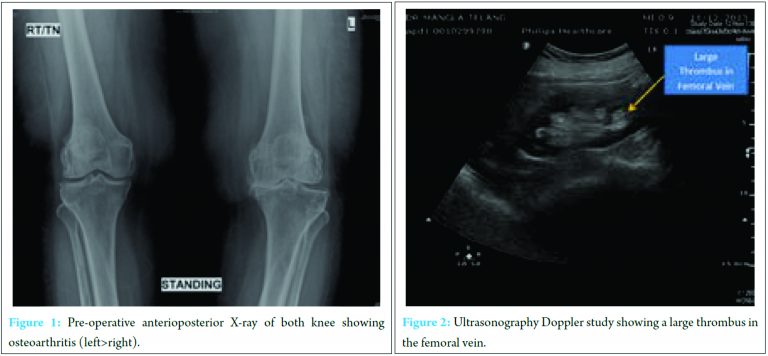

A total of 75-year-old obese female with body mass index (BMI) of 36.5 (obese Class II; according to WHO classification), came with complaint of pain in both knees (left >> right) with difficulty in walking for last 10 years with swelling on left leg for last 1 week. She had severe pain in the left knee which badly affected her activities of daily living. She was a known case of hypertension for last 8 years and hypothyroidism for last 20 years. She was recently diagnosed with diabetes mellitus. X-rays of the left knee (Fig. 1) showed advanced osteoarthritis, and she was advised for left TKA.On physical examination, the patient had swelling and mild tenderness over the left leg without apparent signs of venous thrombosis. Distal pulses of the left leg were feeble and Homan’s Sign was negative. Doppler ultrasound of the lower extremity was done which showed acute thrombosis involving femoral and popliteal vein in the left leg (Fig. 2).